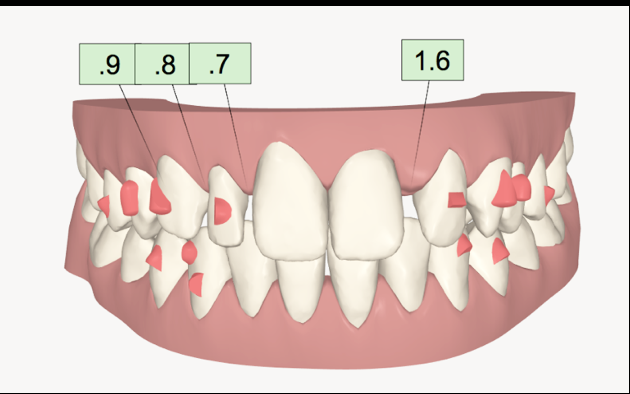

A treatment plan was constructed based on a facially driven smile design, with calibrated images measured against the invisalign clincheck software. The benefit to using a digital system here was to allow for accurate positioning of the anterior teeth for minimal preparation and the ideal restorative outcome. (Figs. 1a-f)

A 7 week invisalign programme allowed for enough movement in the upper arch, while resolving the mild crowing in the lower arch. The final tooth position can be seen in figure 1f.